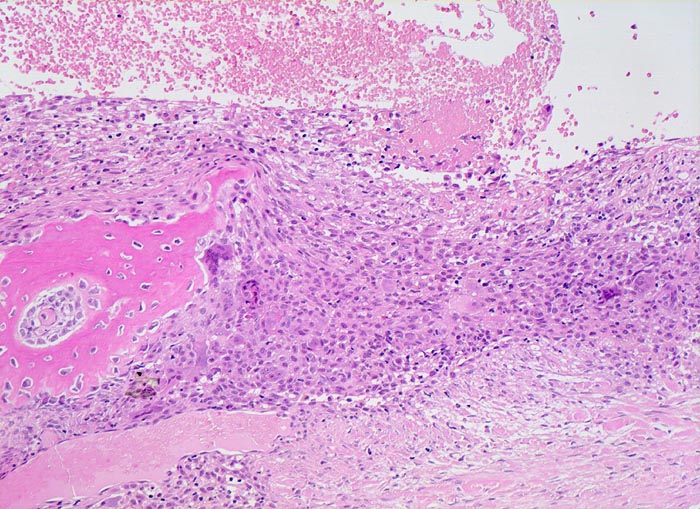

Pseudozystischer Hohlraum ohne Epithelauskleidung gefüllt mit Blut. Die Pseuozystenwand enthält Riesenzellen und mononukleäre Zellen angrenzend an zellarmes kollagenes Bindegewebe. Daneben sieht man neugebildeten Faserknochen.